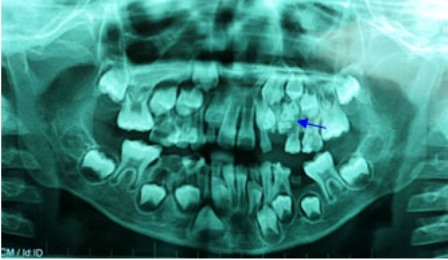

Hình ảnh X-Quang cho thấy túi răng nằm trong miệng bệnh nhi

Qua thăm khám lâm sàng, bác sĩ ghi nhận cậu bé đã mọc được 22 chiếc răng. Thông thường chiếc răng nanh phải mọc trước răng hàm nhưng tại vị trí này là một khoảng trống chỉ có lợi. Bác sĩ đã tham vấn gia đình vì nghi ngờ trẻ bị ngoại lực tác động khiến chiếc răng không thể mọc ra. Tuy nhiên, qua trao đổi ba mẹ bé khẳng định trẻ không bị té ngã, cũng chưa từng nhổ răng.

Bệnh nhi được tiến hành chụp phim X-quang để khảo sát, bác sĩ phát hiện có một khối cản quang ở vùng xương hàm trên bên trái, nằm cạnh khối u là chiếc răng nanh sữa. Qua kết quả trên, bác sĩ chẩn đoán bệnh nhân bị u răng, khối u nằm choán hết đường di chuyển của răng nanh sữa và chắn ngang đường mọc lên của hai răng vĩnh viễn số 3 và số 4.